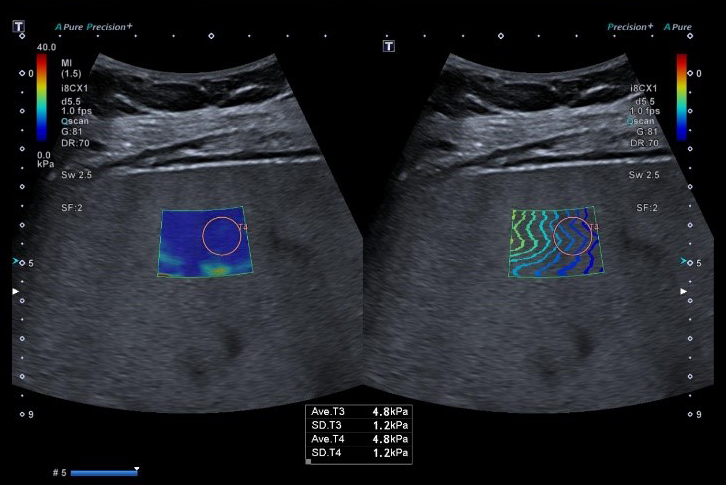

Ņemot vērā, ka SARS-CoV-2 skar daudzus pacientu orgānus, darba ietvaros pacientiem, kuri pārslimojuši COVID-19 infekciju tika veikti krūšu kurvja datortomogrāfijas bez kontrasta izmeklējumi ar 64 slāņu datortomogrāfu ar standarta izmeklēšanas protokolu, un augstas rezolūcijas izmeklējumu potenciāli bojāto plaušu audu rajonam, visiem pētījuma dalībniekiem veikti MR ar 3 Tesla stipru magnētiskā lauka aparātu vēdera dobuma orgāniem, lai diagnosticētu iespējamos bojājumus parenhimatozos orgānos, izmantojot standarta izmeklēšanas sekvences (FSE T2; FSE T1; SPGR in phase, out phase) un difūzijas uzsvērto attēlu (DWI), ar dažādām pieaugošām b vērtībām (50; 200; 800; 1000; 2000), kā arī šķietamā difūzijas koeficienta noteikšanu (ADC). Veikti US izmeklējumi vēdera dobuma orgāniem, limfmezgliem, lai diagnosticētu dažādus COVID-19 izraisītu aknu, nieru un liesas bojājumus, izmantojot standarta izmeklēšanas režīmus (B režīms, krāsu doplerogrāfija) un papildus veikta multiparametriska aknu izvērtēšana ar elastogrāfiju, izmantojot US šķērsviļņu metodi (2D SWE), vērtējot padziļināti aknu fibrozes un viskozitātes pazīmes kvantitatīvi, kā arī steatozes pakāpi. Radioloģiskā atradne tika korelēta ar laboratorisko atradi un klīniskiem datiem.

Projekta ietvaros atklāts, ka COVID-19 pārslimojušiem ir vērojamas izmaiņas aknu viskozitātē, elasticitātē, apstiprina pārciestu aknu bojājumu, kas konstatējams vēdera dobuma utrasonogrāfijas un multiparametrisku aknu izvērtēšanas metodē un būtu ieteicams kā skrīninga izmeklējums seku parādību izvērtēšanā ari turpmāk. Plaušu atrade lielākoties neuzrādīja specifiskas seku pazīmes, kas liecina par plaušu audu augstu atveseļošanās potenciālu pēc pārslimošanas. Citos parenhimatozos izvērtētajos orgānos, limfmezglos specifiskas seku pārmaiņas netika konstatētas.

Aknu multiparametriska kvantitatīva izvērtēšana ar ultrasonogrāfijas metodi